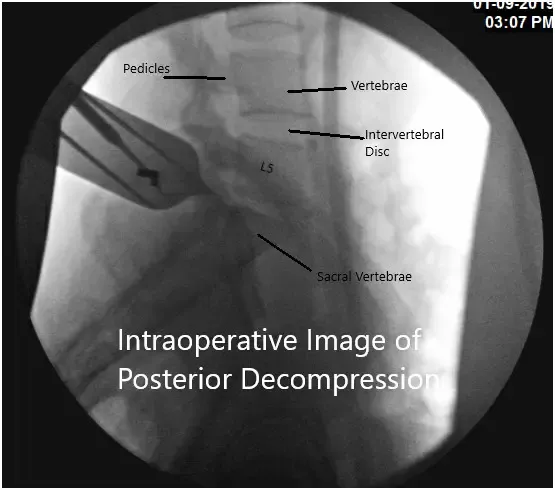

Intraoperative fluoroscopic image.

Preoperative antibiotics were dosed and fluoroscopy was used to localize our incision using a spinal needle inserted at the L5-S1 disk interspace. A #10 blade was used to incise the skin in the midline over the L5-S1 interspace down to the level of the subcutaneous fat.

Thereafter, Bovie cautery was used to continue the dissection along the left laminae of L5 and S1 exposing the interspace. We used a Taylor retractor to hold the muscle and skin edges apart. Using fluoroscopy once again, we confirmed our level of operation. A high-speed electric drill was used to create a foraminotomy at L5 and S1 in order to expose the epidural space.